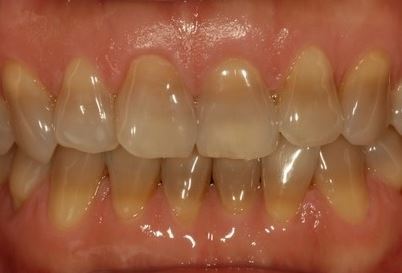

치아 착색의 원인과 해결

치아 착색의 원인은 여러 가지로 나눌 수 있으며, 외부 요인과 내부 요인으로 구분됩니다. 각각의 요인에 따라 착색의 정도와 해결 방법이 달라질 수 있습니다.

2. 내부 요인에 의한 착색

내부 착색은 치아 내부에서 발생하는 변색을 의미합니다.

- 나이: 나이가 들면서 치아의 법랑질이 얇아지고, 그 아래에 있는 상아질이 드러나면서 치아가 점점 노래집니다.